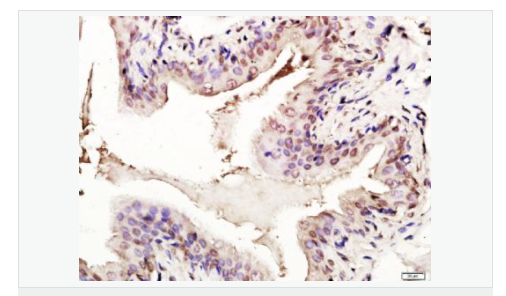

image.png